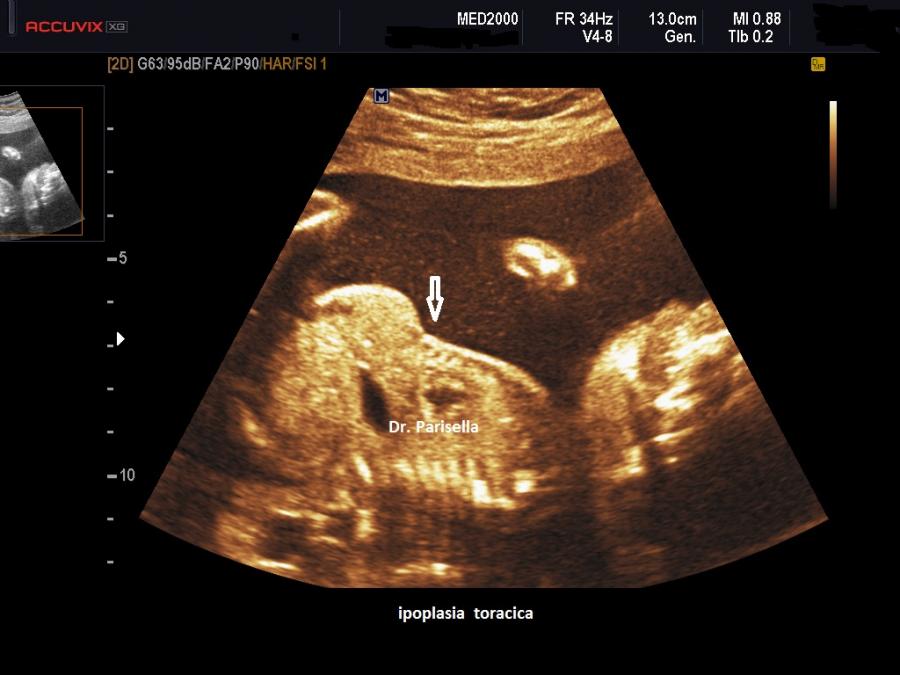

Distrofia Toracica Asfissiante o Sindrome di Jeune OMIM 208500

All'ecografia prenatale si riscontra ipoplasia toracica (torace stretto e coste corte), rizomelia lieve-moderata e frequentemente  displasia renale policistica.